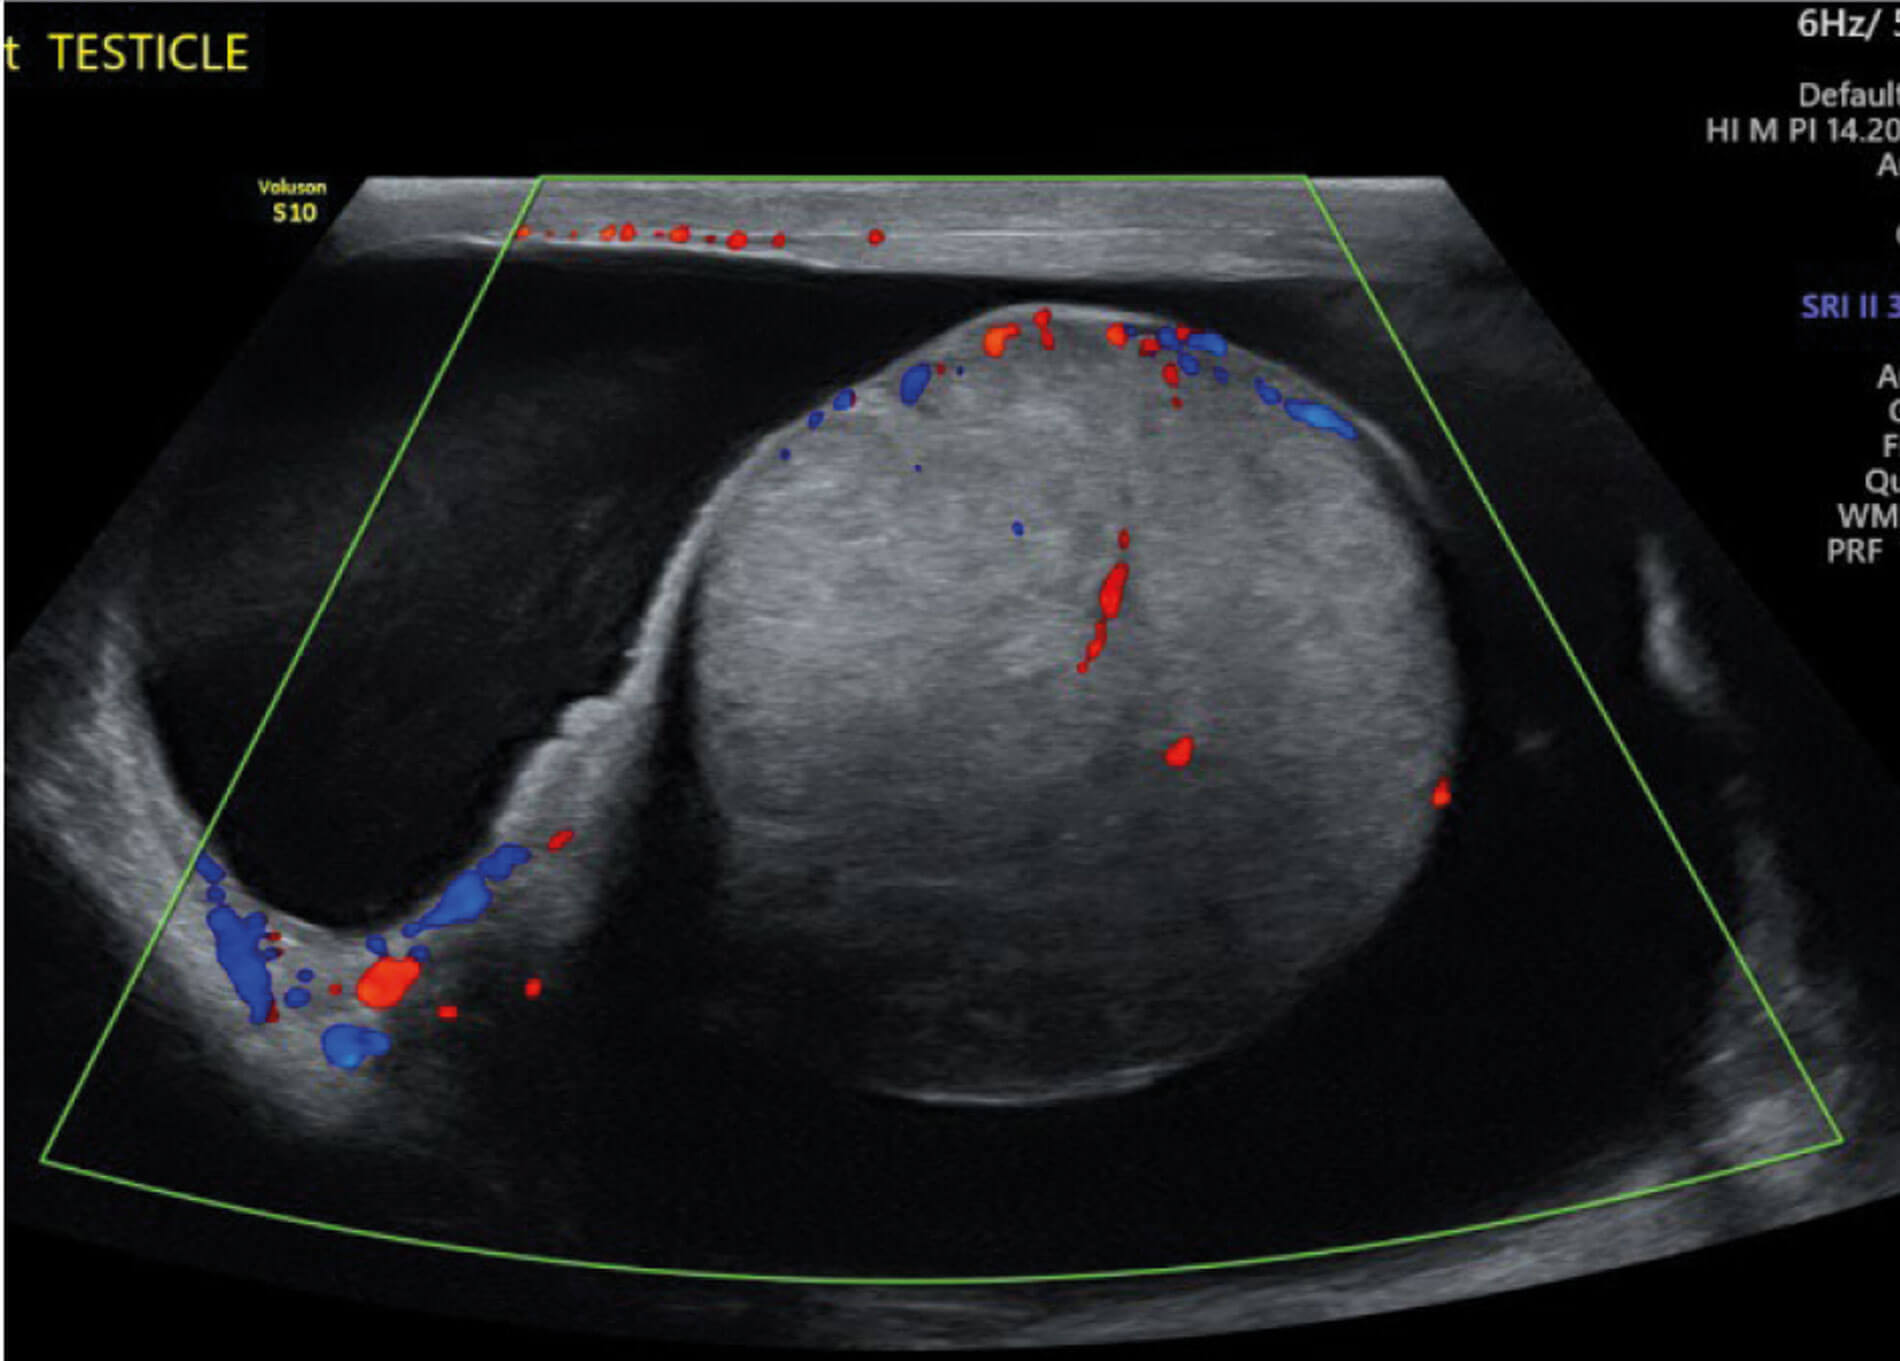

He sought a second opinion from our hospital. A further ultrasound was performed and images were compared. This confirmed a solitary right testis infiltrated by a poorly defined mass of mixed echogenicity. The mass also showed increased vascularity. There was a surrounding hydrocele measuring 100ml with an empty left hemiscrotum.

Figure 3: US in late October 2021.

Figure 4: US in November 2021.